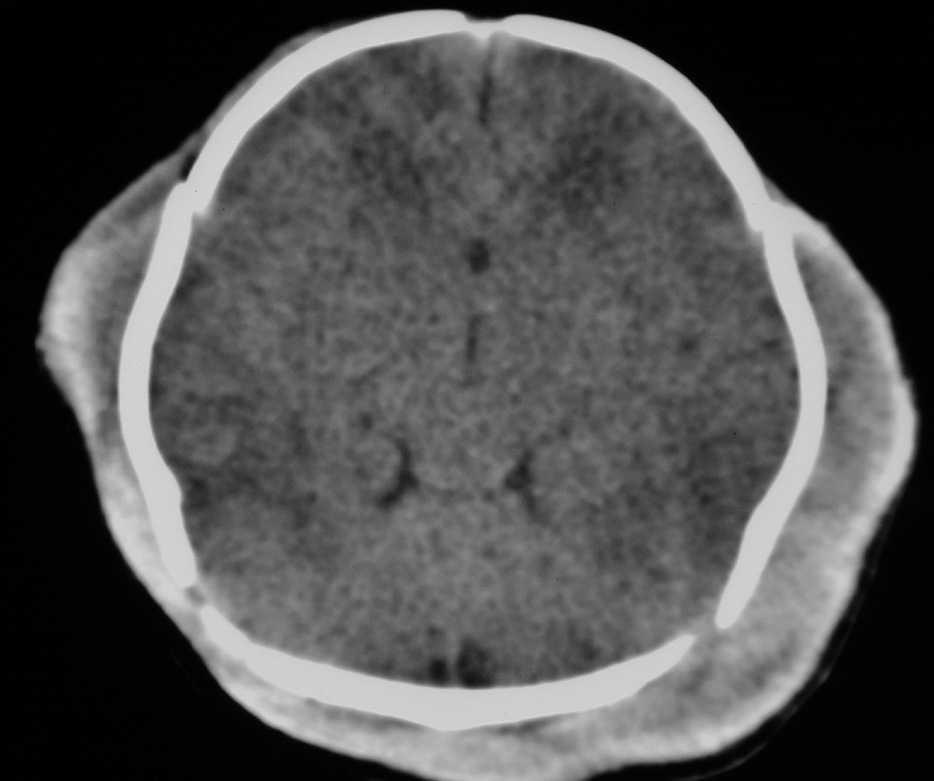

Presentamos un caso de shock hipovolémico hemorrágico en un neonato hijo de madre afectada de tuberculosis, en tratamiento durante la gestación con rifampicina, isoniazida y etambutol. Recién nacido de sexo femenino, fruto de una segunda gestación, cuya madre fue diagnosticada de una pleuritis tuberculosa a las 13 semanas de gestación. Recibió tratamiento con isoniazida, rifampicina y etambutol (I + R + E) durante los primeros 2 meses, manteniendo doble terapia con I + R durante el resto del embarazo, con evolución clínica y radiológica favorable. Los controles ecográficos prenatales fueron normales y las serologías a lúes, HBsAg y VIH negativas, toxoplasma y rubéola inmunes. Parto eutócico, no instrumentado, a las 40 2 semanas. El test de Apgar (al minuto y a los 5 min) fue de 7/9. Se administró profilaxis con vitamina K intramuscular. En la exploración física inicial, en sala de partos, destacaba un distrés respiratorio leve y un caput succedaneum de pequeño tamaño, por lo que ingresó en observación. Presentó deterioro clínico progresivo con taquipnea, taquicardia, quejido e inestabilidad hemodinámica, observando un aumento del tamaño del caput (fig. 1), con acidosis metabólica y anemia. Las pruebas de coagulación demostraron alargamiento del tiempo de Quick y TTPA (tabla 1). Para su estabilización clínica precisó tratamiento con expansores de volumen, bicarbonato, transfusión de hemoderivados (precisando un total de plasma 40 ml/kg y concentrado de hematíes 60 ml/kg), vitamina K y soporte inotrópico con dopamina. La ecografía y TC cerebrales evidenciaron un gran hematoma subgaleal, sin presencia de fracturas ni sangrado intracerebral. El estudio de hemostasia inicial mostró un déficit grave de los factores del complejo protrombínico y vitamina K dependientes (tabla 1). El EEG fue normal y la ecografía abdominal descartó sangrado intraabdominal. El Mantoux fue negativo. La evolución de la paciente fue favorable con normalización de las pruebas de coagulación siendo dada de alta a los 14 días.

Figura 1. TC craneal: se observa importante aumento de tejidos blandos extracraneales compatible con hematoma subgaleal, sin signos de fractura ni sangrado intracerebral.